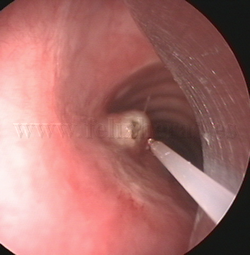

Fotorresección

con láser |